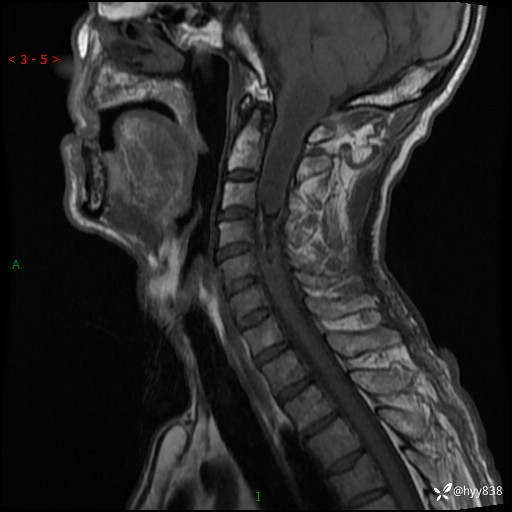

晨读典型病例分享。老年男性,右手麻木3年,四肢无力4月---结果公布~

主诉:右手麻木3年,四肢无力4月

简要病史:患者约于2年前无明显诱因出现右手麻木伴有精细活动差,无行走不稳,家属将患者送至当地县人民医院行颈椎MR提示:颈髓占位性病变。患者未系统治疗治疗。后病情逐渐加重,4个月前出现四肢无力,右侧为甚,行走不稳,伴有四肢感觉减退,伴有大便偶有失禁,现患者及家属为求进一步治疗入我院,遂以“椎管占位”收住我科。 发病以来,患者精神饮食睡眠好,大小便正常,体力体重未见明显改变。

辅助检查:MRI

临床诊断:椎管占位

颈椎MRI平扫(sag T1WI+T2WI-fs+axi T2WI)